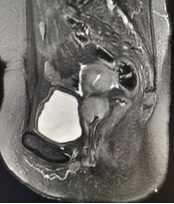

盆腔MRI提示:阴道肿瘤侵犯直肠

查体:阴道肿瘤消退,阴道壁光整部分弹性恢复,右后侧壁局限性深溃疡形成;直肠右前侧壁可触及凹陷。

临床诊断:宫颈鳞癌IIb期放化疗后

阴道转移癌治疗后

直肠阴道瘘